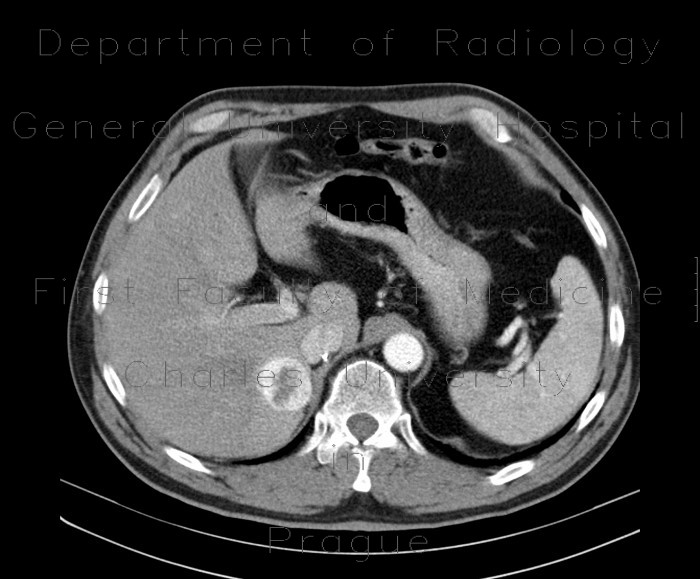

Clinical summary • Male 79 year-old with left renal cell carcinoma and pulmonary metastasis on CT for preoperative staging http://humanhealth.iaea.org ... Retrieve Content